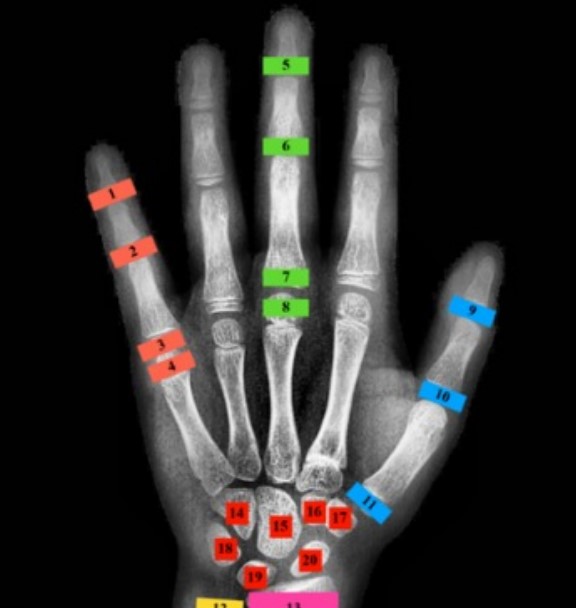

הערכת גיל עצמות מתבצעת לרוב באמצעות צילום של כף יד שמאל ושורש כף היד. קיימות מספר שיטות מרכזיות לניתוח הצילום:

- שיטת Tanner-Whitehouse (TW3): שיטה מורכבת ומדויקת יותר הבוחנת 20 עצמות ספציפיות ומעניקה לכל אחת ניקוד בהתאם לשלב ההתפתחות שלה.